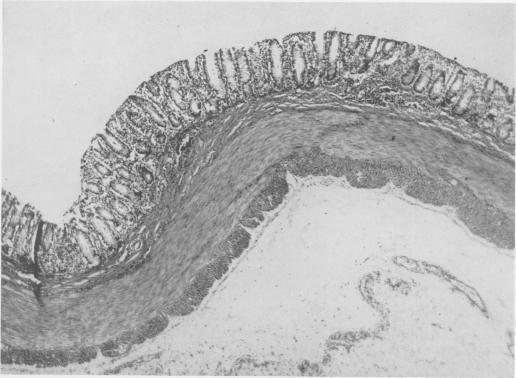

Intestinal obstruction in the newborn caused by agenesis of the myenteric plexus of the entire colon; case report.

Ann Surg. 1956 Dec;144(6):1062-6. doi: 10.1097/00000658-195612000-00019.